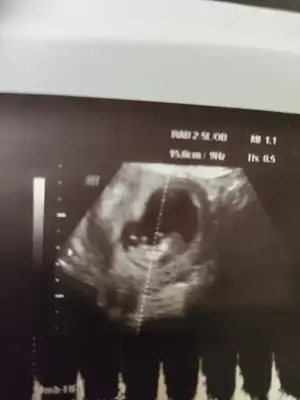

D Dantewn hello ben geldim. 11+3 ultrason fotoğraflarım burada. Doktor emin olamadı nub sanki çıkık ama tam açısında da değil zaten 12 den önce erken dedi ama diğer açıda da eğer o yatay olan nub ise birinci ultrasonla alakası yok. Sence nedir bu küçük ördek?

Bence erkek çünkü kafa yapısı da erkek gibi bacak arası da